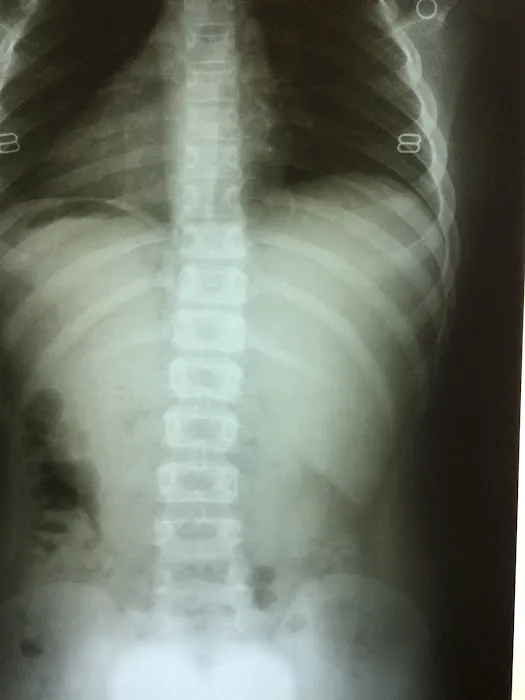

Chiropractic care is a widely recognized health profession focused on the diagnosis, treatment, and prevention of mechanical disorders of the musculoskeletal system, particularly the spine. These disorders can have profound effects on the nervous system and, consequently, on overall health. Chiropractors employ a variety of non-invasive techniques, with spinal adjustments being the primary method, to correct misalignments (often referred to as subluxations) in the spine. By restoring proper alignment and function, chiropractic treatments aim to alleviate pain, improve nerve function, and enable the body's innate healing capabilities. From chronic low back pain and persistent headaches to improving athletic performance and addressing postural imbalances, the benefits of consistent chiropractic care are well-documented by those who experience tangible relief and improved quality of life. It’s not merely about symptom management; it’s about fostering a holistic approach to a healthier, more active, and pain-free existence.

- Spinal Adjustments and Manipulation: Precise, controlled adjustments to correct spinal misalignments, restore joint mobility, and reduce nerve interference.

- Pain Management Solutions: Targeted approaches to alleviate various types of pain, including chronic back pain, neck pain, headaches, sciatica, and peripheral joint pain.